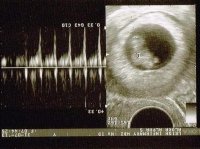

So glad for youMust have been such a relief to see the heartbeat. Could they see where the bleeding is coming from? I hope it stops soon and you go on to have an uneventful boring pregnancy!! (I mean that in the nicest possible way!)

Thank you! It was a massive relief I've got to say. We are both just so happy everything was OK and feel like I can relax now. The bleeding eased off big time as well. fingers crossed. Next scan booked for Wednesday next week.